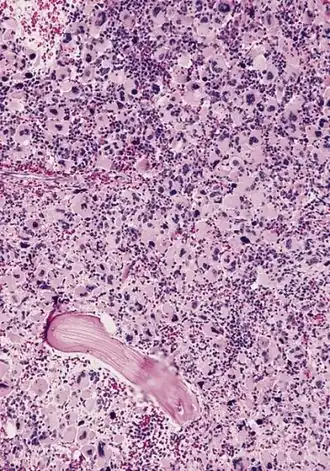

![]() ОМЛ М7, костный мозг на секции | |

Характерная мегакариобластная морфология бластных клеток обнаруживается при морфологическом исследовании аспирата и трепанобиоптата костного мозга, а также мазков крови, в случае наличия в ней бластных клеток. Мегакариобластный иммунофенотип лейкозных клеток устанавливается при помощи проточной цитометрии и иммуногистохимического исследования образцов костномозговой ткани.[11]

В мазках крови и костного мозга мегакариобласты обычно выглядят как среднего размера или крупные (чаще крупные) клетки с большим ядерно-цитоплазматическим отношением (то есть крупным ядром — откуда и название «мегакариобласт») и относительно скудной, вариабельно базофильно окрашенной, цитоплазмой, которая может содержать вакуоли. Ядерный хроматин плотный и гомогенный. Иногда наблюдаются неправильные очертания границ цитоплазмы, и иногда в этих случаях можно увидеть нечто похожее на отшнуровывающиеся от лейкозных мегакариобластов атипичные, «больные» тромбоциты — неправильной формы, малого размера, «тенеобразные». Мегакариобласты отрицательны на миелопероксидазу, и не окрашиваются в чёрный цвет Суданом Б. Мегакариобласты отрицательны на альфа-нафтил-бутират-эстеразу, и могут давать вариабельную (от негативной до резко положительной) окраску на альфа-нафтил-ацетат-эстеразу, обычно в виде отдельных пятен или гранул в цитоплазме. Окраска на PAS также вариабельна — от негативной, через фокально-пятнистую или гранулярную, до резко положительной. Аспират костного мозга во многих случаях сложно получить из-за наличествующего у многих больных с ОМКЛ миелофиброза. Более точная идентификация ОМКЛ возможна с использованием электронного микроскопа и/или иммунофенотипирования на характерные для мегакариоцитов антигены CD41 и/или CD61), что может позволить поставить правильный диагноз. Также диагнозу способна помочь цитогенетика на характерную транслокацию [t(1;22)(p13;q13);] и выявление характерных молекулярных аномалий, таких, как наличие фузионного онкопротеина RBM15/MKL1 или мутантной формы GATA1.[12]